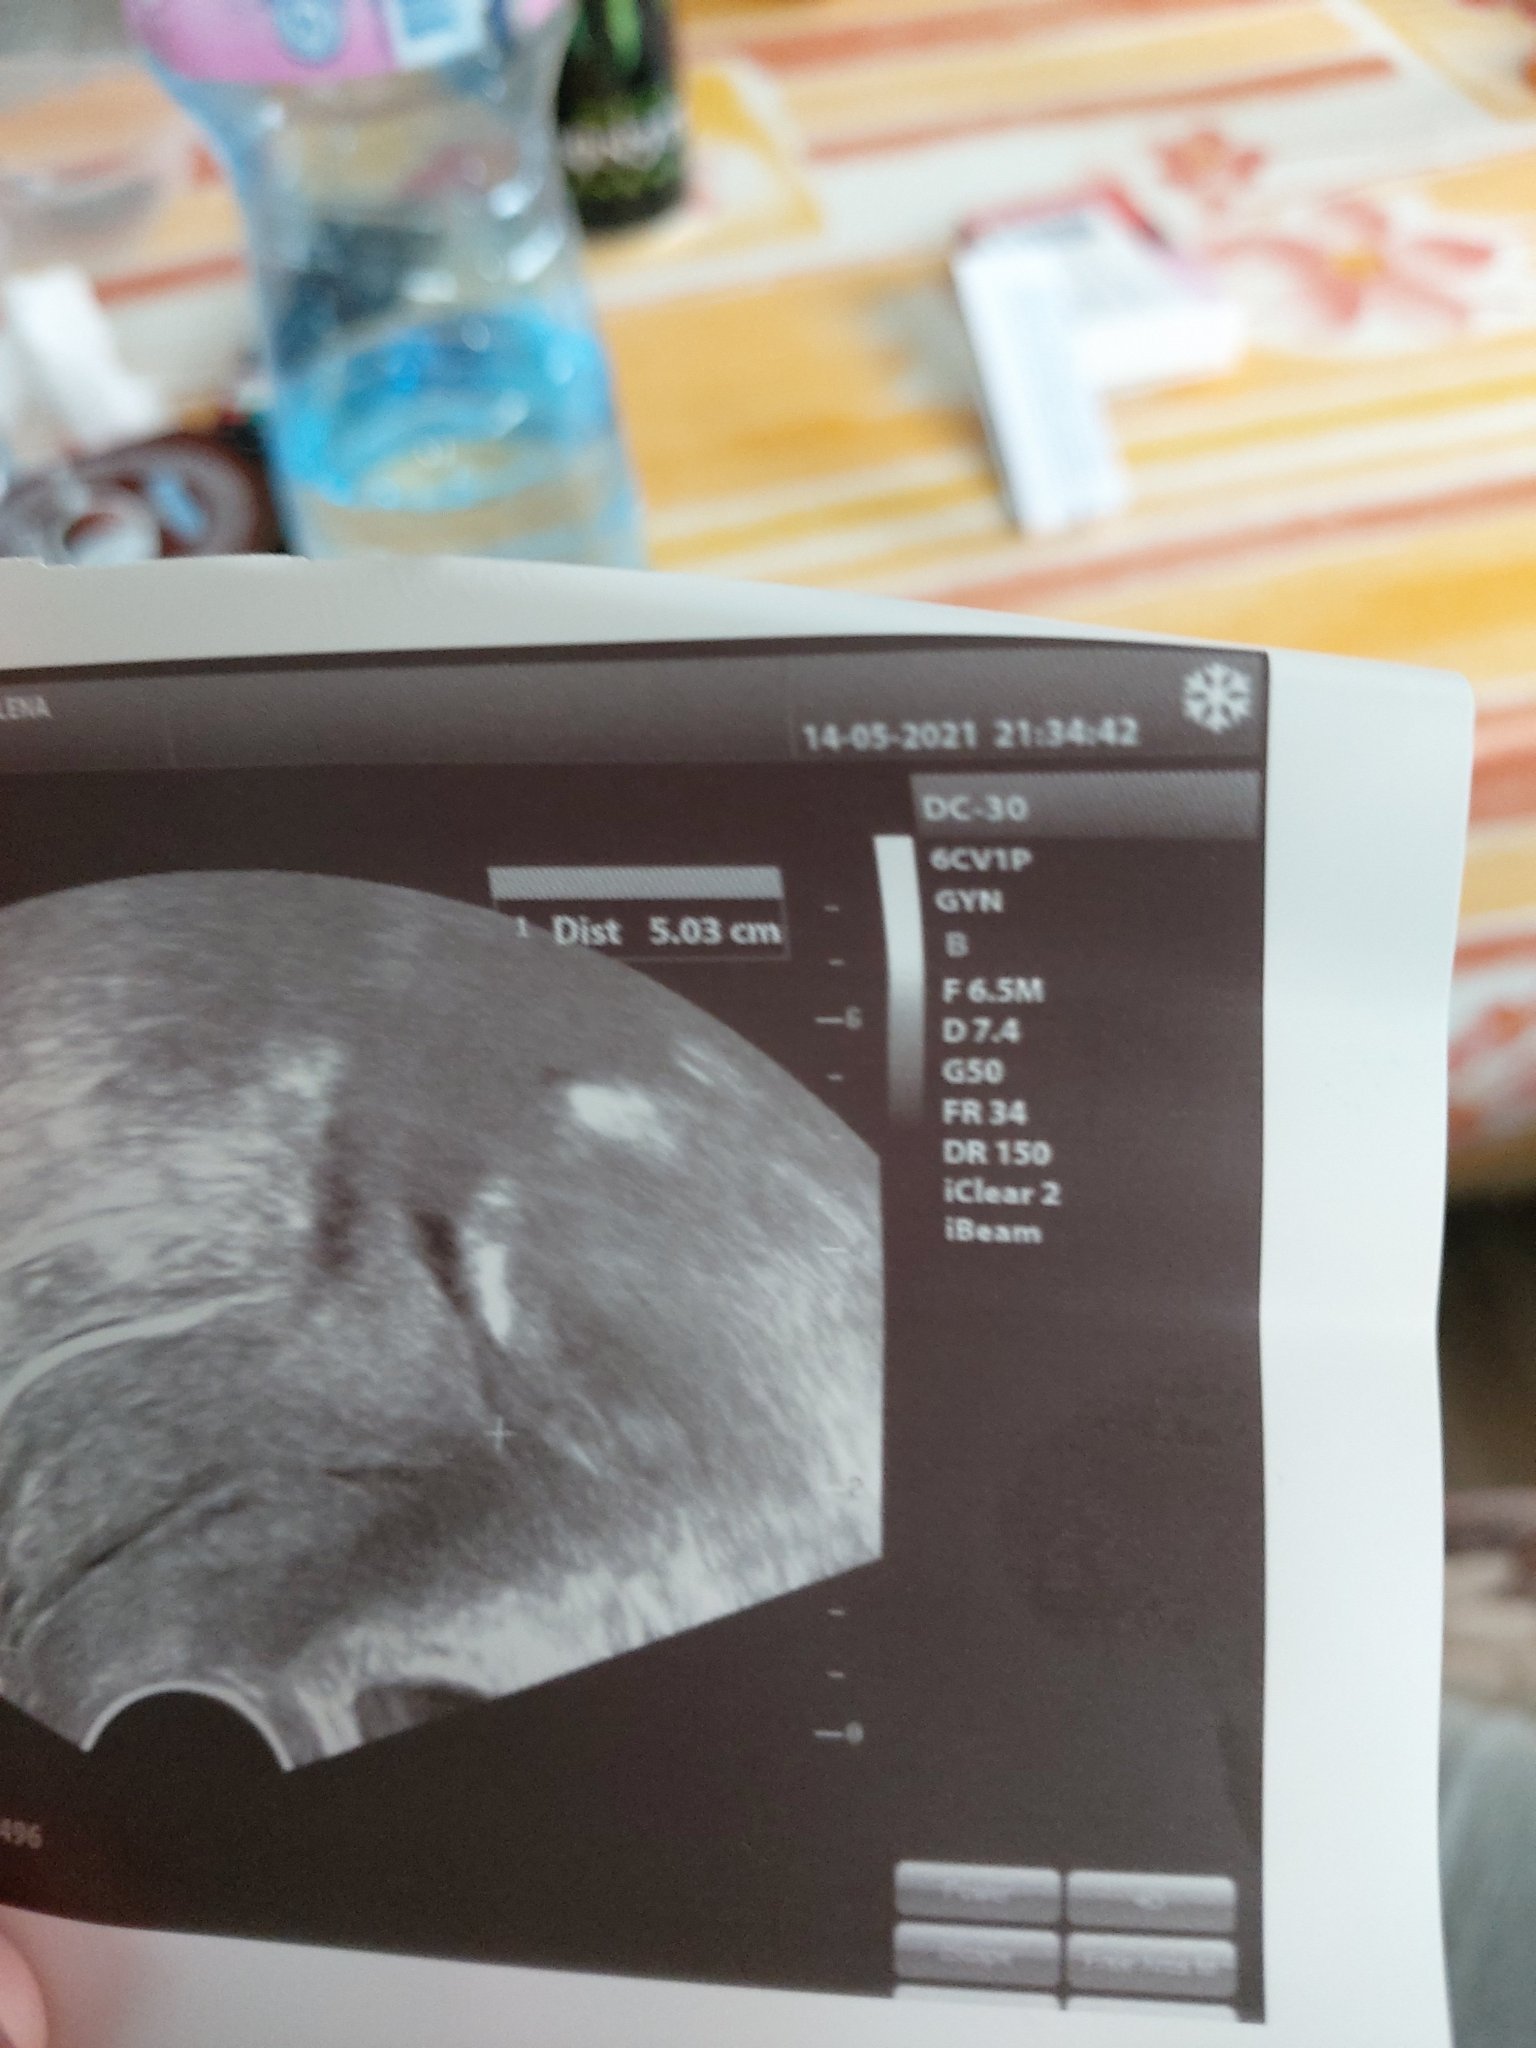

ето и снимкато от шийката казаха че е перфектна .